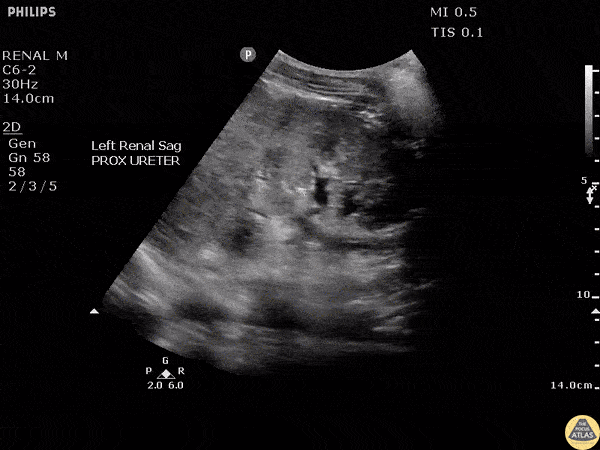

A young female presented to the ED with flank pain and a fever. Ultrasound revealed the urothelial lining of the renal pelvis was >2mm suggestive of a recent underlying obstructive process. Image courtesy of Robert Jones DO, FACEP @RJonesSonoEM Director, Emergency Ultrasound; MetroHealth Medical Center; Professor, Case Western Reserve Medical School, Cleveland, OH View his original post here